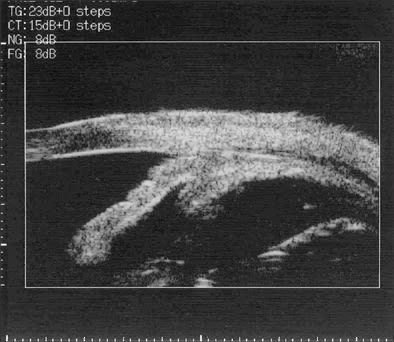

On postoperative day 2, the retinal lesions showed demarcation, suggesting regression of the active process (Figures 4 and 5). Her vision in OD had now declined to 20/600. Keratic precipitates were noted to regress in size and number. The retinal lesions continued to decrease over the course of the 10 days with a concomitant improvement of her vision to 20/400, so that we were comfortable to discharge the patient on oral acyclovir 800 mg 5 times per day. Acyclovir therapy was maintained over a total of 3 months. At 6 months postoperatively, we opted to remove the silicone oil during cataract surgery on her right eye. Subsequently, ocular hypotony developed in OD with choroidal detachments (Figure 6), which required a silicone oil refill. An aspirate from the vitreous cavity obtained during the latter procedure was again positive for V. zoster immunoglobulin A by immunofluorescence assay, which prompted us to resume oral acyclovir therapy with 400 mg 3 times per day, along with 8 mg prednisone po and prednisone ointment twice per day for her right eye.

| Figure 6. Ultrasound images showing detachment of ciliary body (left) and choroid (right) due to ocular hypotension. | |